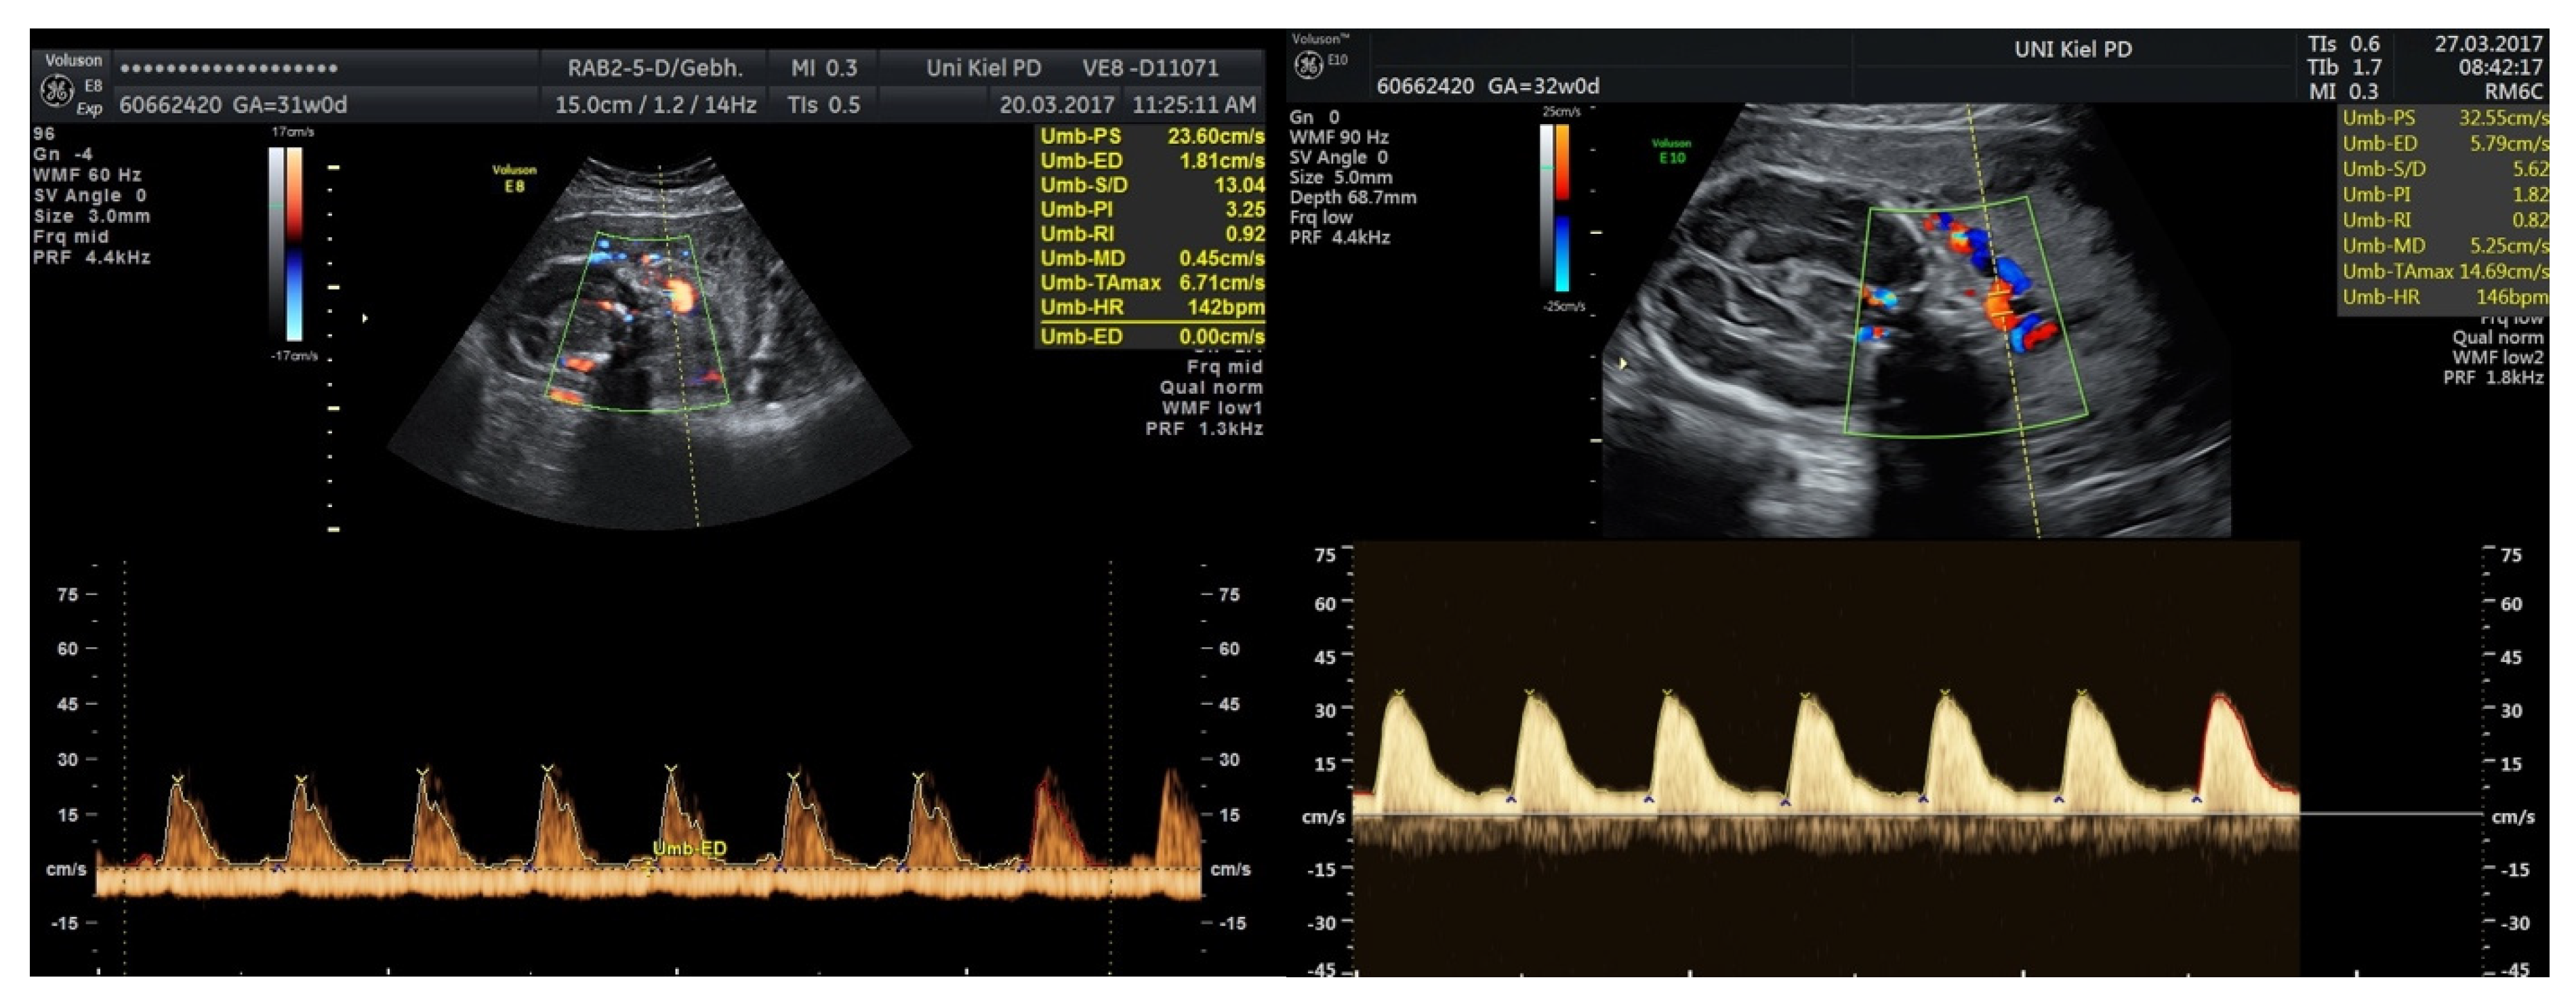

3.3.2. Fetal Growth Restriction

4.4. Fetal Growth Restriction